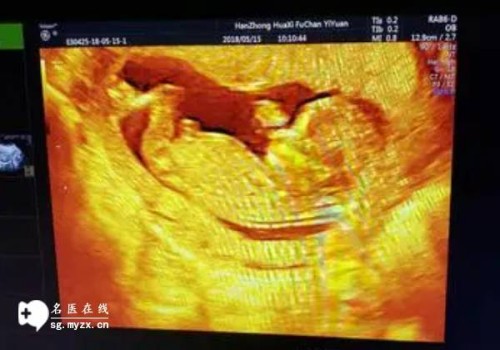

- 如果想明确诊断,可以选择尿妊娠试验、血HCG试验,或者b超检查。如果明确有怀孕,就要定期做孕期检查,保证孕妇和胎儿的健康。同时要补充适当的营养,保持充足的营养,对孕妇和胎儿都有好处。

中医脉象一般在怀孕后40到50天左右能感觉到。喜脉的特点是脉搏平稳,不涩不滞,脉率相对比平时要快。这时候就可以把脉。但是怀孕后的具体时间每个人都不一样,值得注意的是,并非所有的脉滑都是怀孕。女性也可能在月经期或刚吃完饭后或运动后出现滑脉。所以建议女性在月经推迟后,可以去医院抽血检测HCG,或者做尿孕检和腹部b超来确定是否怀孕。女性怀孕后要注意保持心情愉快,睡眠充足,不要做剧烈运动,不要有性生活,以免先兆流产。